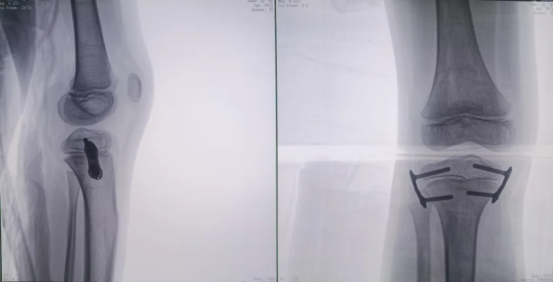

Preoperative Imaging

Intraoperative 3D images were acquired by the Perlove Medical’s 3D C-arm.

During the procedure, the positioning guidewire is inserted into the growth plate. A 3D scan is then performed by the 3D C-arm to confirm the guidewire's placement. Once verified, the plate is attached and secured with cannulated screws.

A final C-arm fluoroscopy check showed satisfactory positioning of the “eight-Plate” and proper screw direction. The wound was irrigated with saline, sutured, dressed, and immobilized with a brace, marking the completion of the procedure.